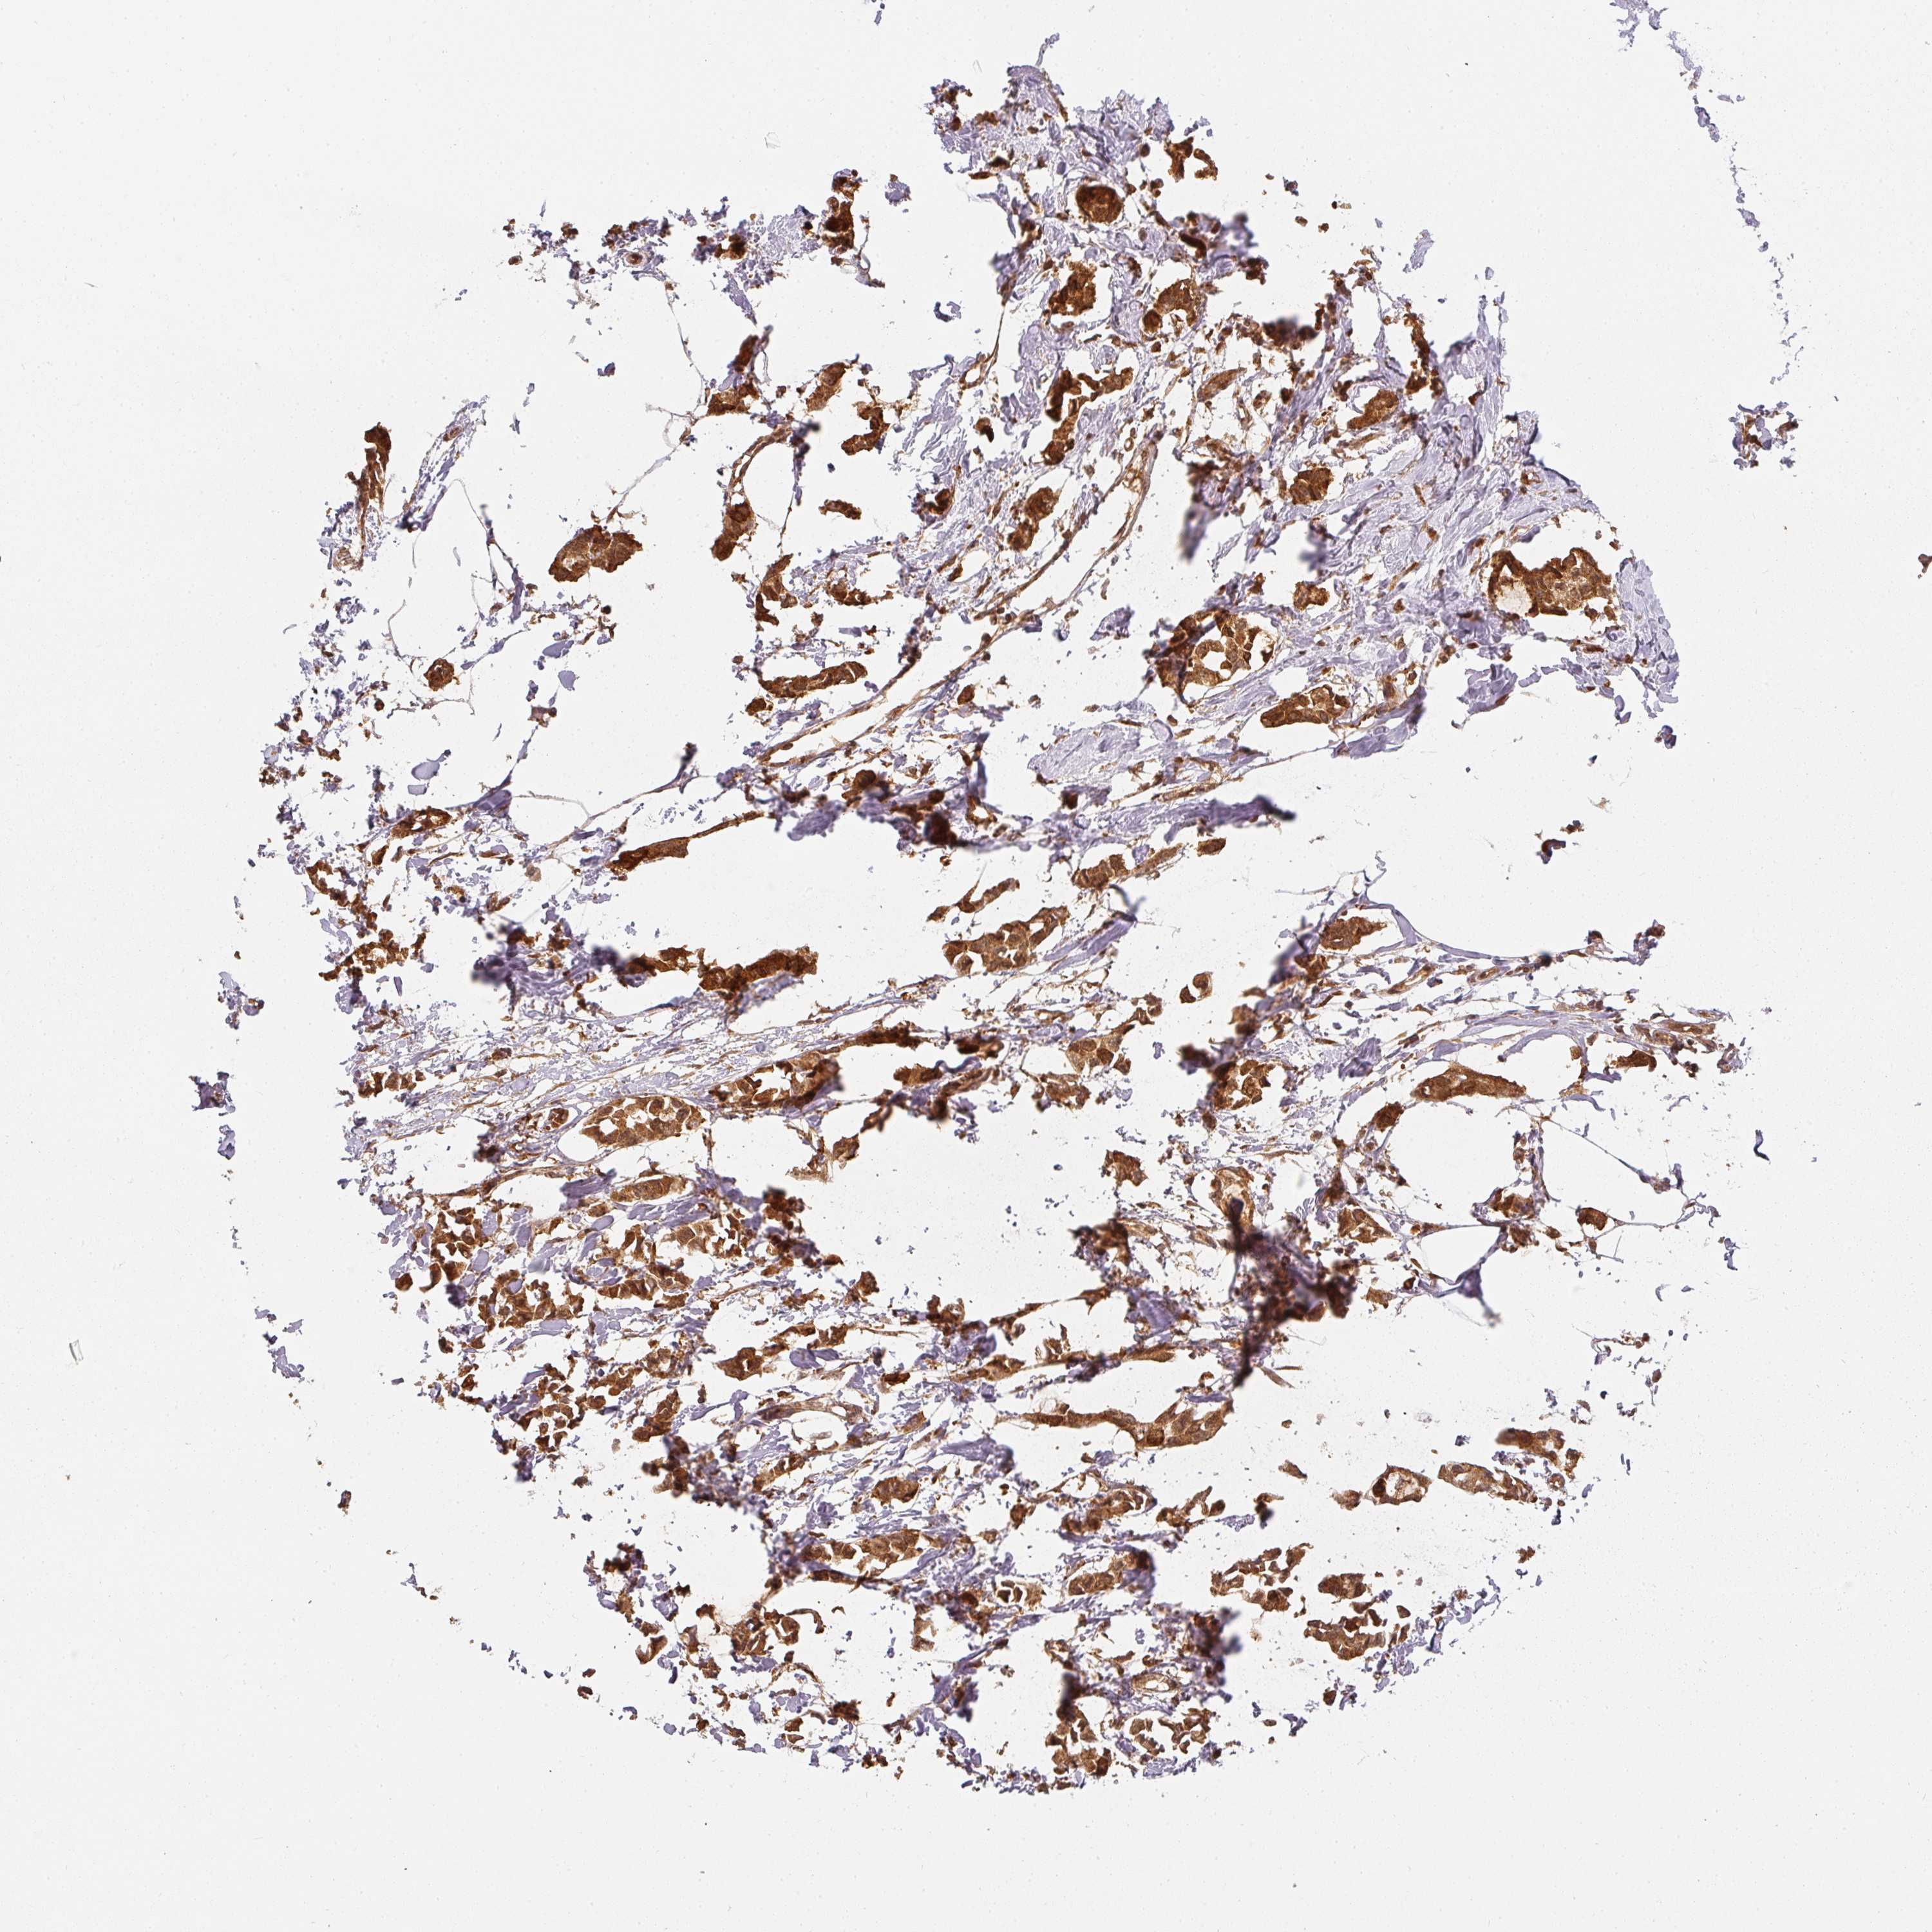

CANCER BREAST CANCER Show tissue menu

BRCA TCGA BRCA VALIDATION PROTEIN EXPRESSION

Breast cancer

Human cancer

Breast invasive carcinoma

PPP6R3 is not prognostic in Breast Invasive Carcinoma (TCGA)